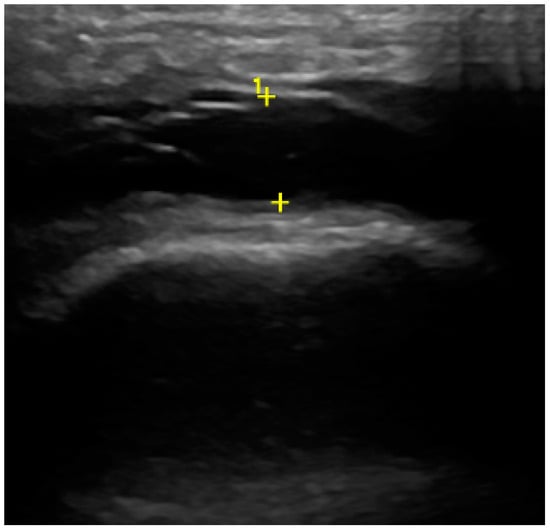

In the US analysis, we aimed to assess synovial effusion within the joint, which is indicative of inflammation or pathological fluid accumulation (Figure 2). Additionally, a thorough examination of the osseous structures was conducted. This included identifying the presence of osteophytes and evaluating any erosive changes to the bone surfaces. Furthermore, the analysis extended to the evaluation of the articular disc (Figure 3). For the purposes of the study, a unique research protocol was proposed, consisting of the assessment of the temporomandibular joint in the neutral position (mouth closed) with the mouth in maximum opening and the assessment of the path of the articular disc movement in a dynamic test. All examinations were performed by the same experienced radiologist using a LOGIQ E10 ultrasound with a dedicated L8-18i hockey stick linear probe (GE Healthcare, Boston, MA, USA).

Figure 3. Ultrasound (articular disc—black arrow, osteophyte—white arrow).